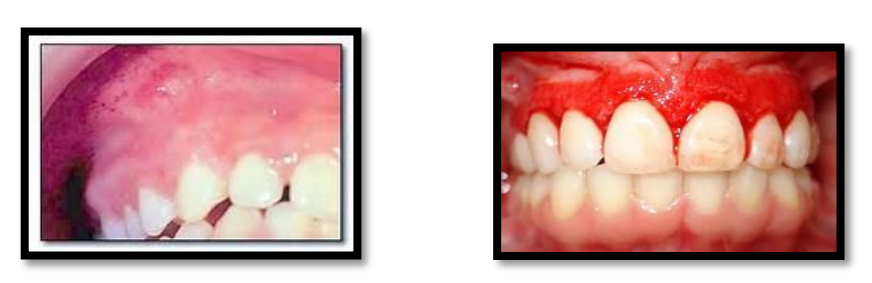

- En présence de signes hémorragiques (pétéchies, hématome, gingivorragies), une thrombopénie peut être suspectée, justifiant la prescription d’une numération plaquettaire (NP).

-Un diabète est suspecté devant des antécédents familiaux de diabète, des signes généraux et des signes oraux (gingivites persistantes, parodontites sévères, candidoses, aphtes, poly caries, sécheresse buccale, retards de cicatrisation,